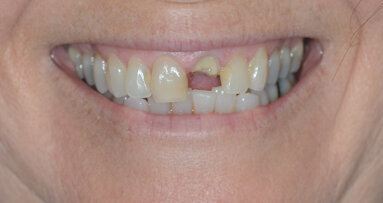

This case report highlights a novel method of restoring implants utilising the modern advances in digital intraoral scanning and chairside milling. It illustrates how an aesthetic single implant retained crown can be provided chairside without the need for analogue impressions (Figs. 1 & 2: Pre-operative condition).

In conclusion, as you can see in the final result (Figs. 27–29) an aesthetic, biologically designed and durable restoration has been fabricated. The patient has been delivered the final restoration in a single visit without the need for traditional analogue impressions.